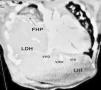

Ante la condición crítica inestable del paciente se fijó el pequeño remanente posterolateral del diafragma a la parrilla costal, como paliativo hasta una segunda intervención en mejores condiciones. En la reintervención, a los 7 días, se comprobó defecto diafragmático muy extenso a través del cual protruía el hígado fusionado a un pulmón muy hipoplásico, los cuales eran densamente adherentes sin un plano de separación identificable, compartiendo parénquima y vascularización. La arteria pulmonar era muy delgada, no se observó vena cava inferior y las venas hepáticas drenaban directamente en la aurícula derecha, lo que se comprobó posteriormente en la angiotomografía (fig. 1).

Se decidió cerrar el defecto alrededor del hígado, sin intentar separar la fusión. El remanente del diafragma se suturó a la cápsula hepática con puntos horizontales de polipropileno 4/0, reforzados con almohadillas de politetrafluoroetileno (GORE-TEX®) constituyendo un sello efectivo para evitar la hernia de las asas intestinales. La cúpula del hígado quedó a la altura del IV espacio intercostal como en una eventración diafragmática (fig. 2).